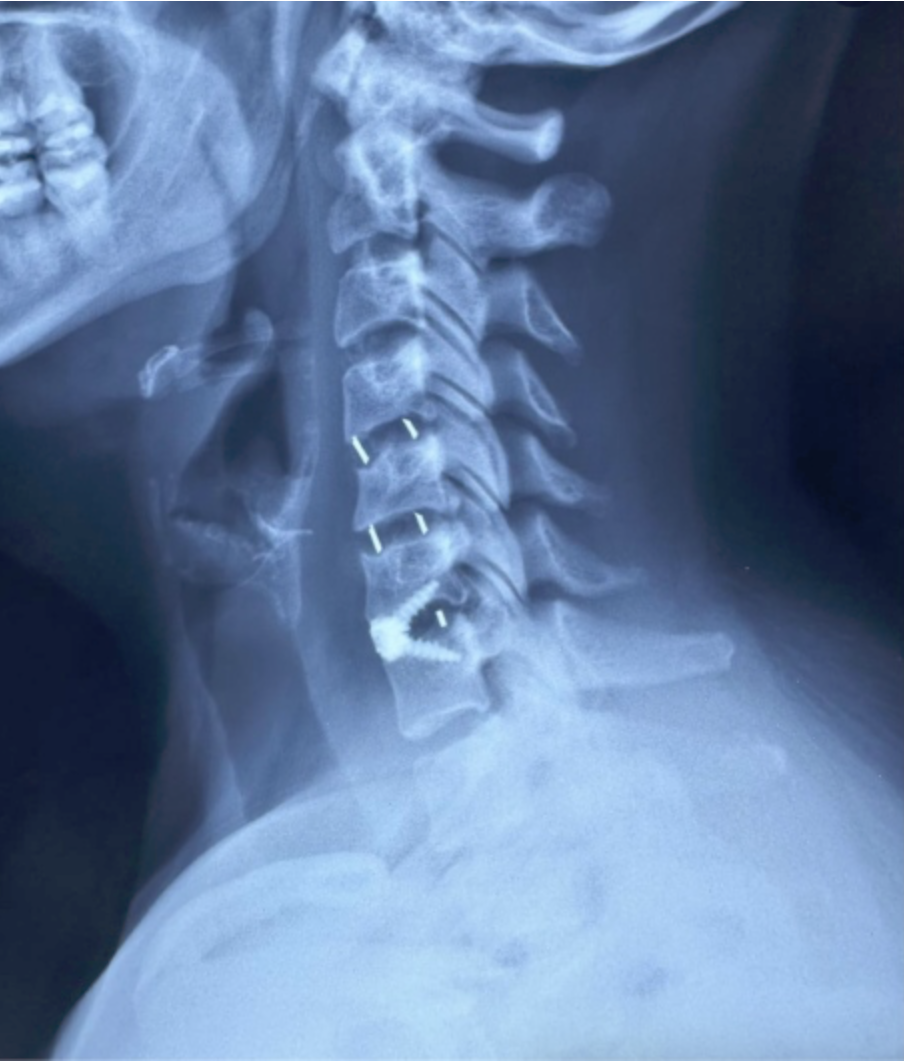

RESULTADOS